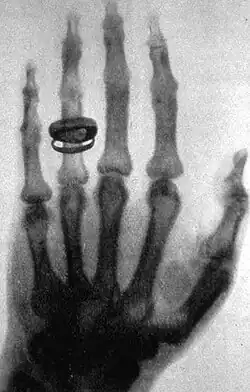

An X-ray picture (radiograph), taken by Wilhelm Röntgen, of Albert von Kölliker's hand.